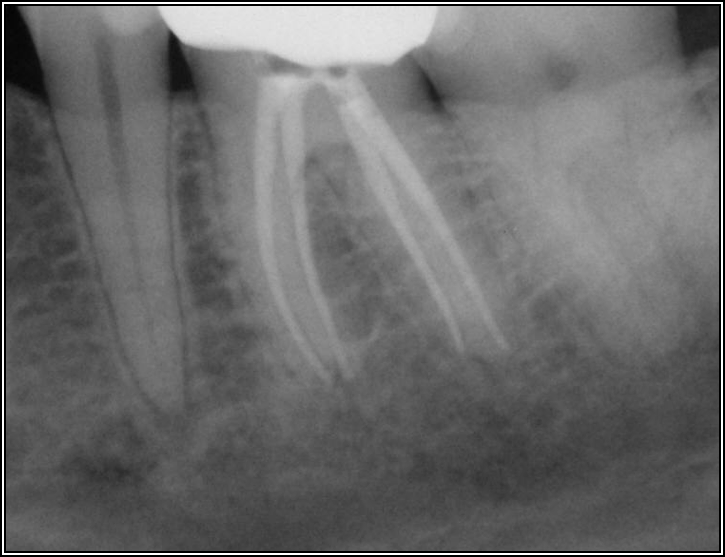

Figure 6 shows the successful root canal that stopped the patient from being in pain, but she still had some discomfort. The images did not show anything significant; the case was completed at a time when cone-beam computed tomography (CBCT) was not routine. The clinicians had to trust what they saw, which was 6-mm probing that left a chance for a crack in the tooth. There was a buccal fracture of the mesial root. There was bone apical to it but nothing coronally, so they decided to resect the root. They cut it out, put some holes into the bone, and added demineralized freeze-dried bone. They also later put a collagen membrane over it and closed it.

Fig 7. Bruxism.

Figure 7

Fig 8. Bitewing revealed decay and other problems.

Figure 8